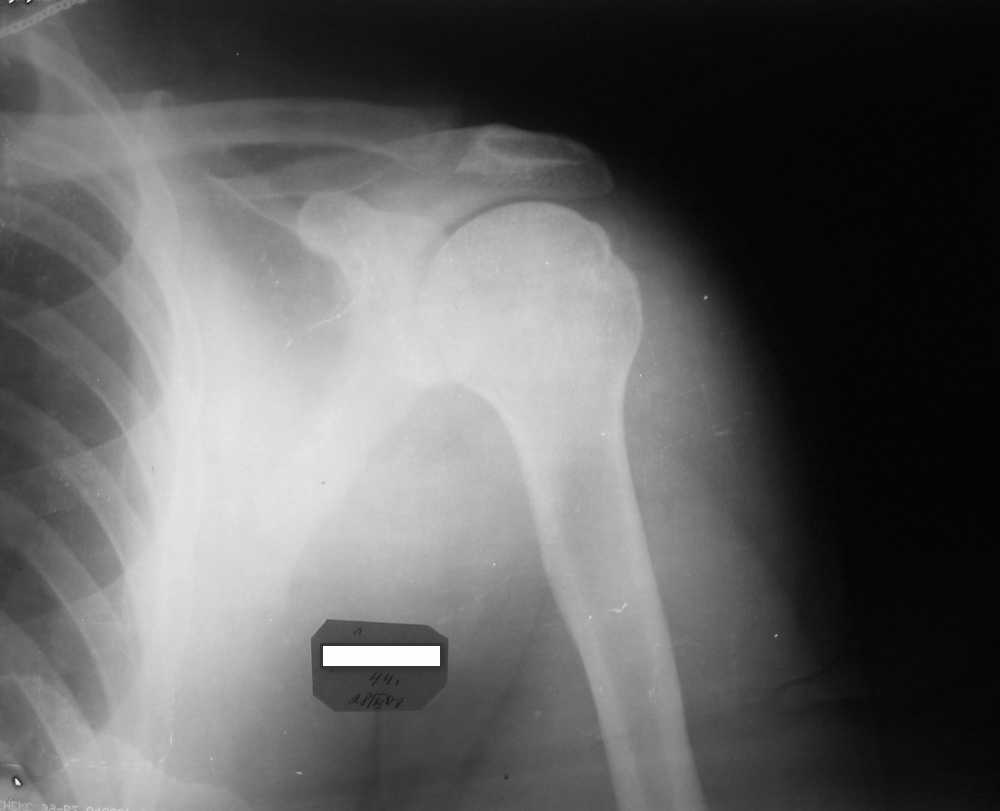

Мужчина, 45 лет. Профессионально занимается культуризмом. При жиме лёжа

возникают резкие боли в левом ключично-акромиальном сочленении в течение

3 лет. В покое болей нет.

Имя     : IMG_3097.jpg